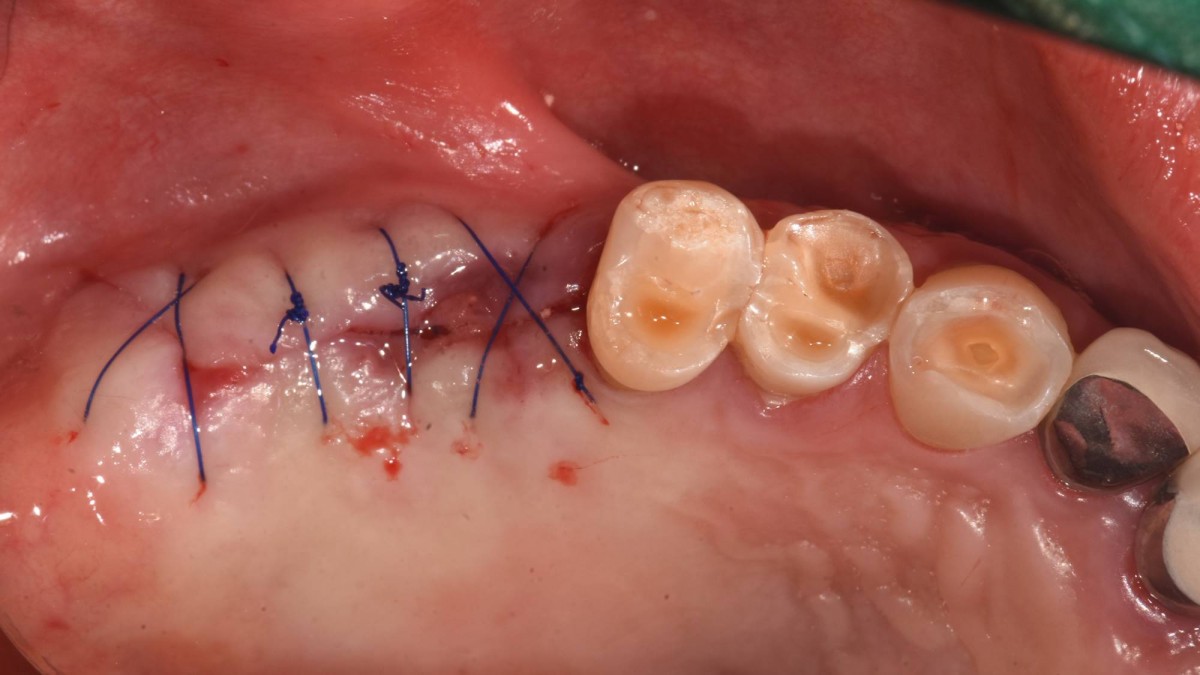

Socket Lift and Implant Placement in the right maxilla.

<GCacg> A 56-year-old male patient complained of pain in the right upper and lower jaws. And he wanted the upper first molar to be pulled out first.